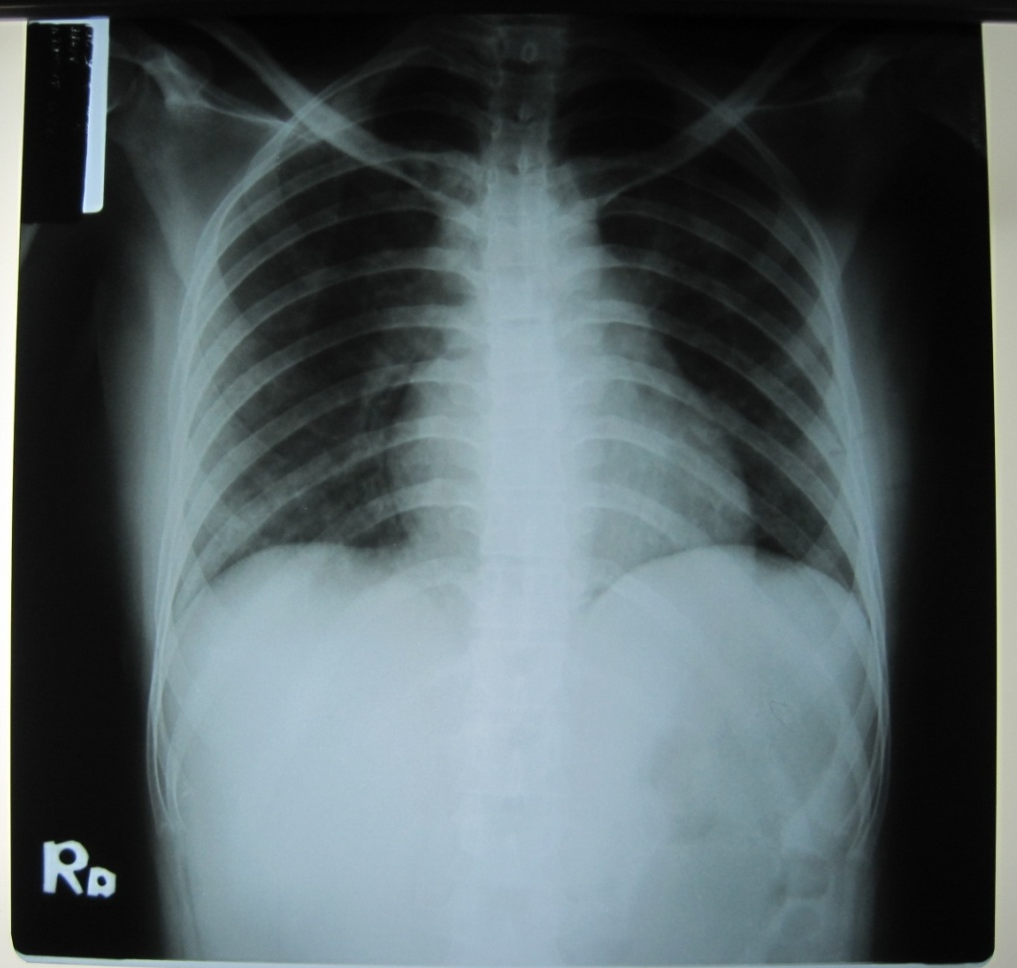

The patient showed seriously ill, dyspnoe/chest discomfort, compos mentis, blood pressure 100/60 mmHg, pulse rate 104 x/minute regularly, respiratory rate 26 x/menit, 37.5 °C axillar temperature. On the Eye, Ear, Nose and Troat there were no abnormalities found, no Lymph node enlargment, no oral candidiasis and no cardiac abnormality. On the chest auscultation, we found bronchovesicular breath sounds; additional sound was rales at the left and right lungs, no wheezing. The Chest X-Ray impression: bilateral bronchopneumonia (fig. 2).

Fig. 2: Chest radiograph (Chest X-Ray)